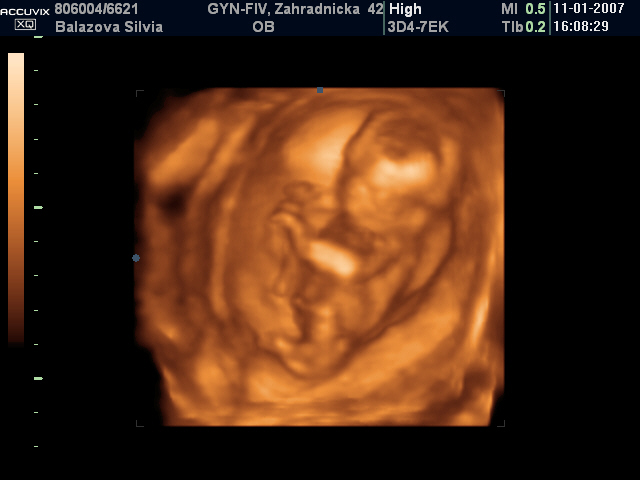

Silvia Balážová{{_AND_}}Štefan Baláž